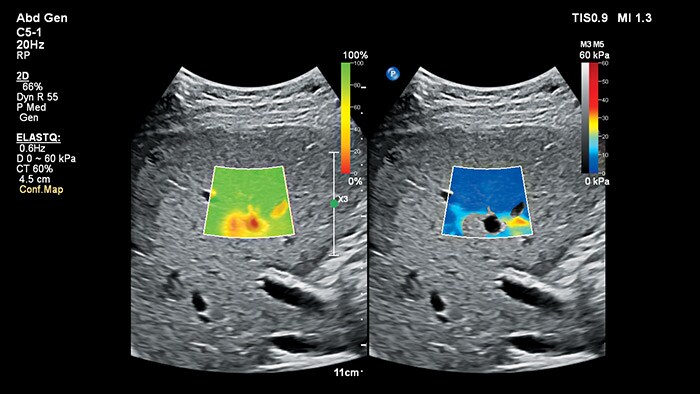

ElastQ Imaging

ElastQ Imaging ermöglicht die Echtzeit-Beurteilung der Gewebesteifigkeit mit großem Sichtfeld – ideal für Kinder, die möglicherweise schwer schallbar sind.